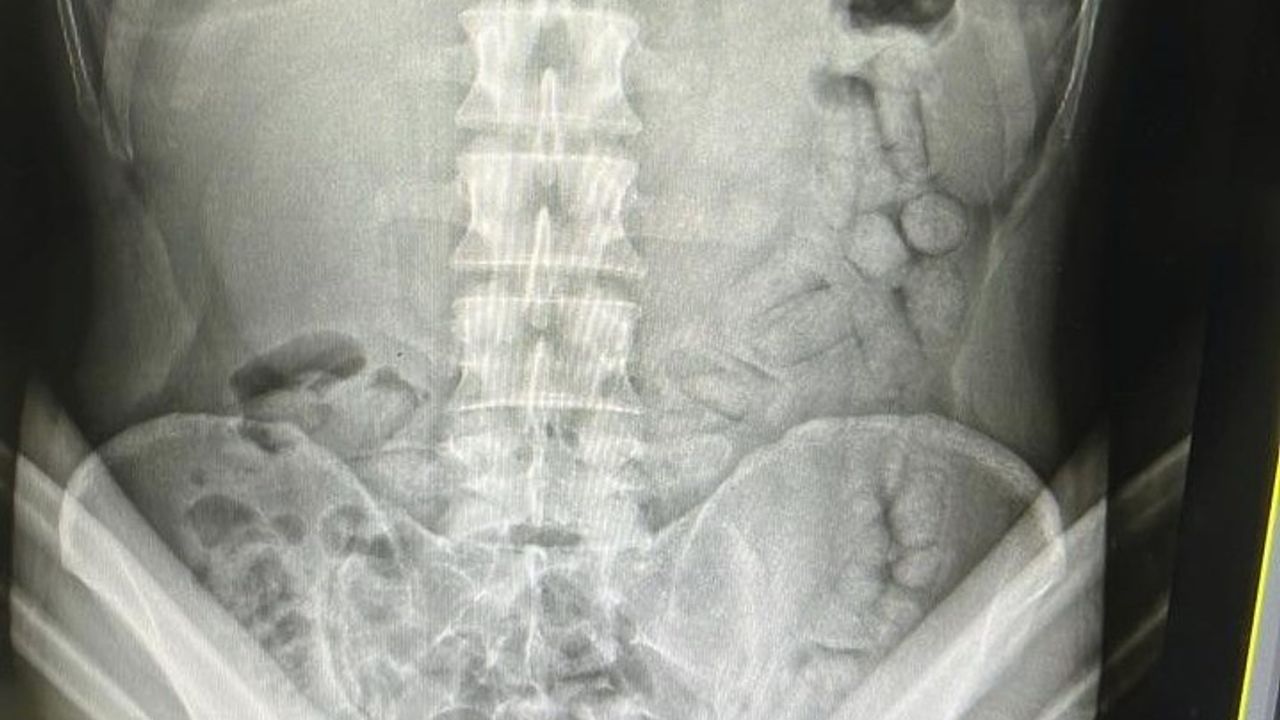

Adli makamların talimatı üzerine Gümüşhane Devlet Hastanesine götürülen şahsa yönelik iç beden muayenesinde bağırsaklarında 55 adet kapsül olduğu tespit edildi. Hastanede yapılan müdahalenin ardından şahsın bağırsaklarından çıkarılan kapsüllerin içerisinde toplamda 317,46 gram metamfetamin ele geçirildi.